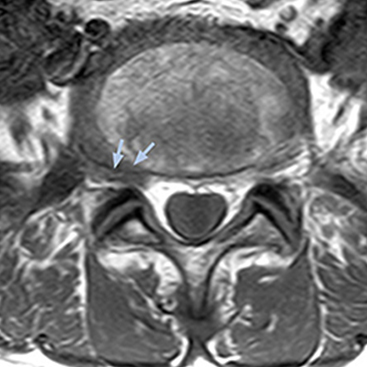

“Although symptoms of typical disc herniation and atypical hernia are very similar, the actual site of herniation is different. It is therefore important to characterize the nerve’s condition both inside and outside of the intervertebral foramina. “Conversely, if we see no abnormality in NerveVIEW, we can assume at least that there is no severe condition that requires surgery. Like this, it can help us avoid unnecessary surgery. NerveVIEW can have a tremendous impact in this way.”

“NerveVIEW is really useful for those cases where a nerve disorder is strongly suspected based on the clinical examination but our regular MRI images do not show any findings. These atypical herniations and spinal canal stenosis, occurring in 5% to 15% of the total lumbar herniation/stenosis cases are our main target when using NerveVIEW,” says Dr. Yabuki.

“The intra-luminal signal of veins, especially around the intervertebral space, can be suppressed well with NerveVIEW. As a result, we can easily observe the detailed nerve structure around the posterior ganglion,” he says. “This is why we use 3D NerveVIEW for intraforaminal stenosis and extraforaminal stenosis/herniation (lateral disc herniation). On the other hand, if herniation is suspected to exist inside the dorsal root ganglion (DRG), balanced TFE or ProSet-FFE is applied. NerveVIEW is not suitable for evaluating the median type of herniation.” The SE-EPI DWI-based method for MR neurography works well for large FOV exams like whole-body MRI, but focal examination of nerves is often limited by the attainable spatial resolution (both inplane and slice direction) and geometric distortion. “3D NerveVIEW achieves higher in-plane resolution – close to our other routine spine sequences – and the source images can be used instead of adding a fat-suppressed T2-weighted sequence,” Tanji says.